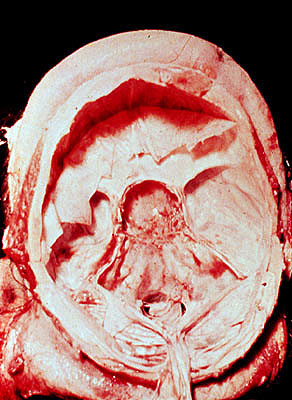

Effects of pituitary macroadenoma, enlarged sella

Enlargement of bony sella (under protracted pressure

atrophy

), autopsy.